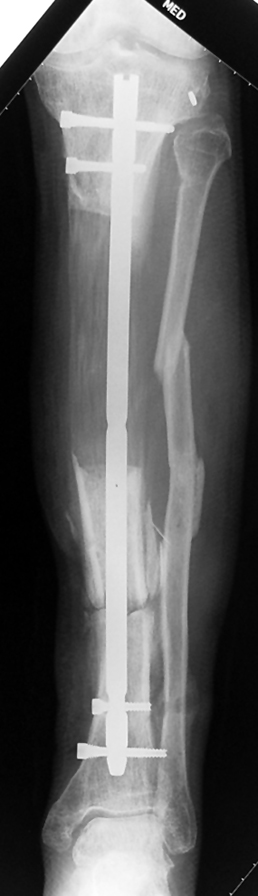

The duration of external fixation (external fixation index) depends on the amount of distraction required, and the extremity is prone to complications during this period. After the distraction phase is completed, the external fixator remains in place during the consolidation phase, which lasts twice as long as the distraction phase; but this period is hardly tolerated. If the external fixator is removed before sufficient consolidation is achieved, fractures, deformity and shortness will be the result. In our department, ‘lenghthening over nail’ method is used in order to decrease the external fixation index and increase patient comfort and activity level. In this method, the intramedullary nail is statically locked after the completion of the distraction phase, and external fixator is removed. The extremity is stabilized by the intramedullary nail during consolidation phase. In this way, complications due to long external fixation index or early removal of the external fixator are avoided.

Case 1